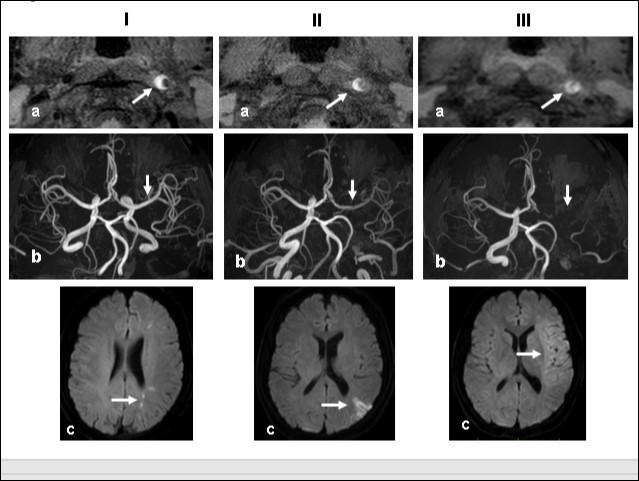

This 43-year-old Japanese male presented with right hand dysesthesia. He has not recognized his neck pain and Horner’s syndrome( oculosympathetic palsy). Magnetic resonance imaging(MRI) performed on a 3T TX scanner (Philips Achieva, The Netherlands) demonstrated dissection of the left cervical carotid artery (CCA; Figure 1A,1B ); no ischemic area was detected in the left cerebral brain. Axial section views of the CCA segment revealed a typical crescent hematoma; a bright, hyper-intense circle representing the narrowed arterial lumen was visualized. A T1-volumetric isotropic turbo spin echo acquisition (VISTA) sequence resulted in the diagnosis of dissection of the CS-ICA (Figure 1C). He had no conventional stroke risk factors such as hypertension, diabetes, hyperlipidemia, a history of cardiac valvular disease, arterial fibrillation, or features of inherited connective tissue disorder. Also absent was a history of arterial trauma and we were unable to identify any etiological factor(s). One week later he developed Gerstman symptoms; border zone ischemia was observed in the left cerebrum (Figure 2-Ic). He was admitted and the administration of antiplatelet agents was started. The left middle cerebral artery (MCA) was supplied via antegrade circulation (Figure 2-Ib) and an increase in the flow-void intensity was noted (compare Figure 1C with Figure 2-Ia). MRI studies acquired one week later revealed spreading of the ischemic area to beyond the watershed zone between the left anterior cerebral artery (ACA) and the MCA, and the MCA and the posterior cerebral artery (PCA) (Figure 2-IIc). The area of dissection had spread from the ICA bifurcation to the top of the ICA. The blood supply to the left MCA territory derived from the circle of Willis (Figure 2-IIb). The flow-void intensity had increased further (compare Figure 2-Ia with Figure 2-IIa). Two weeks after his admission he suddenly experienced complete right-sided hemiparesis with motor aphasia. MRI performed within 45 min demonstrated diffuse ischemia in the left MCA territory (Figure 2-IIIc), the left A1 segment could not be visualized. The left MCA and its A1 segment were completely occluded (Figure 2- IIIb). The flow-void intensity indicated complete occlusion of the true lumen (Figure 2-IIIa). He underwent emergency left superficial temporal artery (STA)-MCA bypass surgery within 6 hours; double anastomosis was successful. External decompression was performed to prevent neurological deterioration due to severe brain swelling. An intensive rehabilitation has been continued for him after operation. His functional independence measure (FIM) score recorded over the course of 4 months showed remarkable improvement ( Figure 3) as did the standard language test for aphasia.

Figure 2.Time course Columns I, II, and III are images obtained 1, 2, and 3 weeks, respectively, after the start of dissection of the cervical segment of the internal carotid artery. Ia, IIa, IIIa.T1 VISTA images of the same segment shown in Fig. 1C. The dark area reflective of the low void progresses to hyperintensity by week 3. IIIa shows complete occlusion of the true lumen by the intramural hematoma (arrow ). Ib, IIb, IIIb. TOF-MRA images of the intracranial arteries. (a) The left MCA is supplied via antegrade flow from the left carotid artery (arrow). (b) Flow from the left carotid artery disappeared from the ICA bifurcation to the top of the ICA. Blood supply to the left MCA derives from the circle of Willis via the anterior- or the posterior communicating artery (arrows). By week 3, flow to the left MCA, even via the left A1 segment of the anterior cerebral artery had disappeared completely. Ic, IIc, IIIc. Diffusion-weighted images at the basal ganglia level. Week 1: a few hyperintense areas are visualized in the border zone of the left cerebrum (arrow). Week 2: Note the hyperintensity area in the watershed zone between the left ACA and the MCA, and between he MCA and the PCA (arrow). The image acquired on week 3 shows a diffuse hyperintensity area in the left MCA territory (arrow).